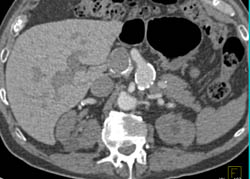

Active Bleed in Right Lobe of Liver